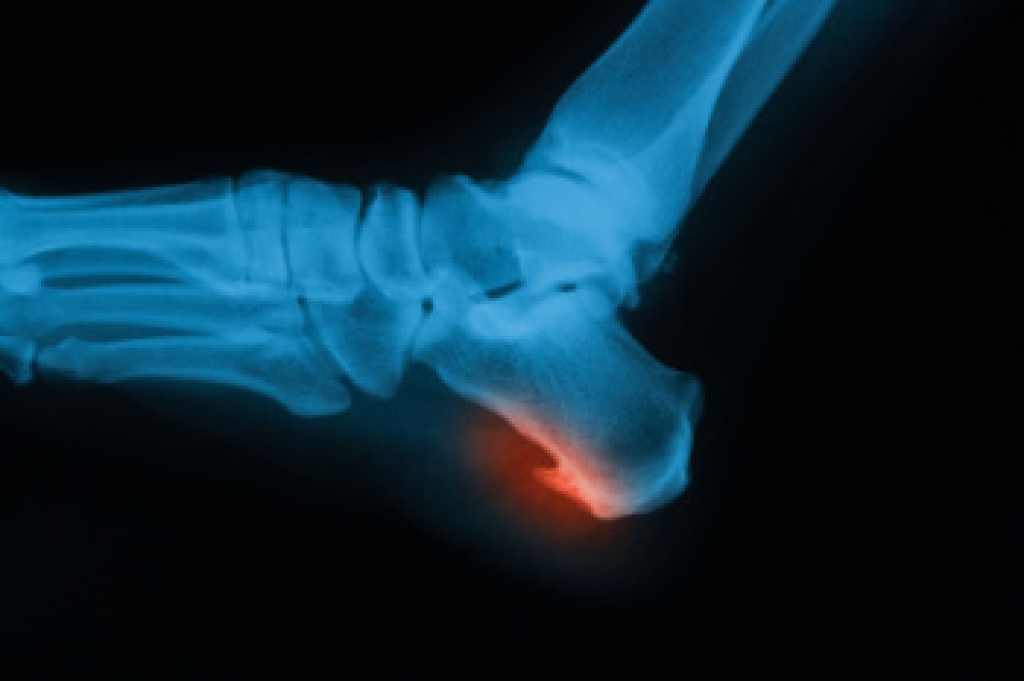

Bunions and bunionettes are deformities of the toes. A bunion occurs as a bony lump on the outside of the big toe. It causes the tip of the toe to excessively angle towards the other toes. A bunionette occurs on the pinky toe. Symptoms of a bunion or bunionette are a bulging bump on the side of the affected toe, swelling or redness around the toe, restricted movement, physical discomfort or pain, numbness, and difficulty walking. Both bunions and bunionettes can be caused or made worse by wearing poorly-fitted, tight, or uncomfortable shoes. Orthotics can help ease the pain associated with bunions and bunionettes by distributing the weight of the body evenly along the surface of the foot and relieving pressure on the affected toes. To find out if orthotics may help you with your bunion pain, please consult with a podiatrist.